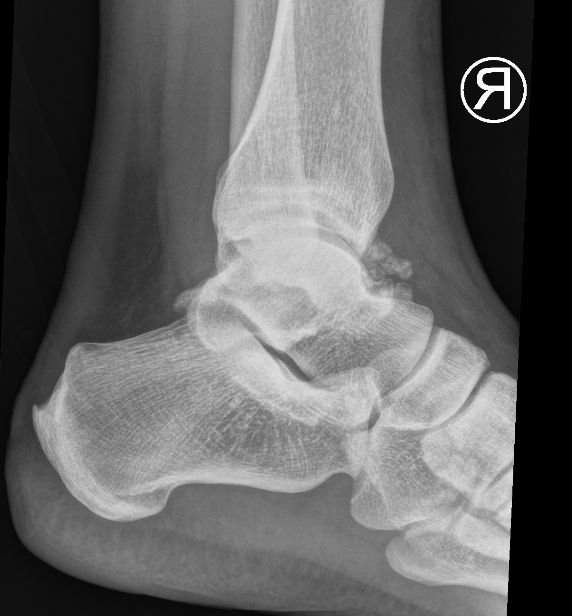

X-ray

Demonstrate calcified lesions / synovial osteochondromatosis